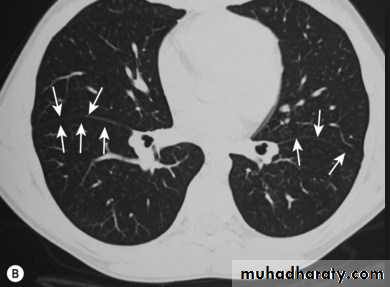

HRCT is thin section high spatial resolution CT, use for pulm. Parenchymal dis. And bronchiectasis.

5- bronchiectasis.

6- diffuse pulm. Disease.

Only structures seen normally in CT scan of chest are blood vs., fissures and walls of bronchi(as on CXR).

Most metastasis and granulomas are located peripherally where blood vs. are smallest.

Fissures seen as line or as avascular zone